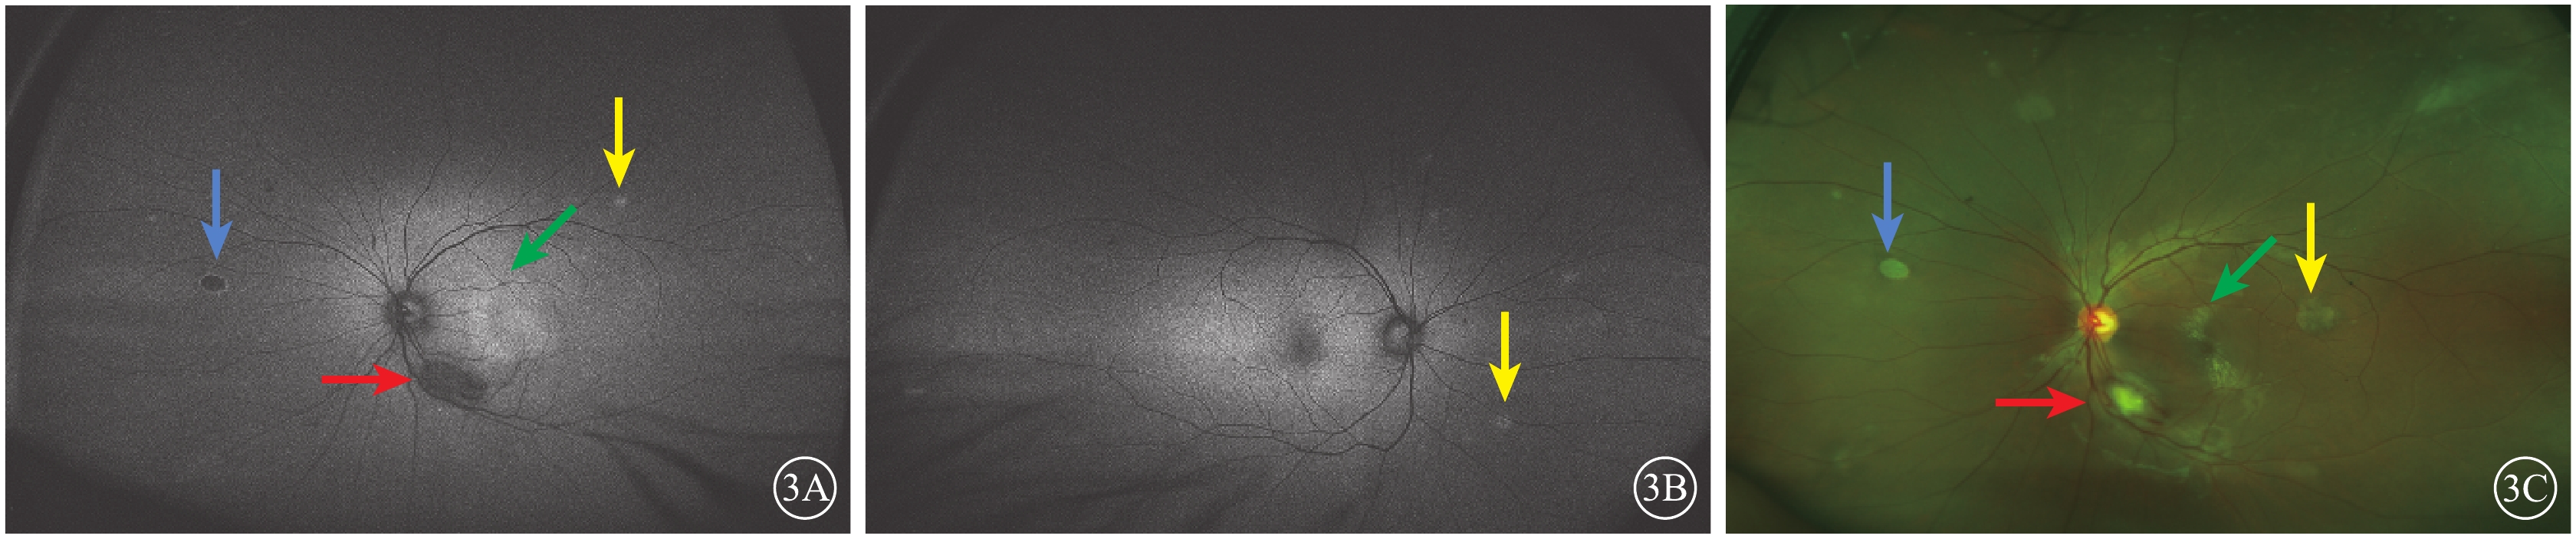

眼底自身熒光(FAF)檢查,左眼視盤顳下約1 DD大小的弱自身熒光(AF),黃斑區呈強AF,范圍約3 DD,鼻側萎縮灶弱AF伴強AF環繞,隱約可見幾處片狀稍強AF(圖3A)。右眼中周部視網膜數處強AF團塊(圖3B)。超廣角眼底彩色照相檢查,左眼視盤顳下1 DD大小團塊狀黃白色病灶,病灶周邊可見血管紆曲;與FFA上病灶對應區域可見數處散在小片狀淡黃色半透明病灶,病灶遮蓋部位視網膜血管稍模糊,黃斑區可見圓形滲出性視網膜脫離區域(圖3C)。右眼上方血管弓處及鼻側周邊及上方周邊可見與左眼相同表現的病灶。

圖3

患者雙眼FAF像及左眼超廣角彩色眼底像。3A.左眼FAF像,黃斑區強熒光(綠箭),顳下病灶弱熒光(紅箭),鼻側萎縮病灶弱熒光伴強熒光環繞(藍箭),隱約可見幾處片狀稍強AF(黃箭);3B.右眼FAF像,中周部視網膜數處強AF團塊(黃箭);3C.左眼超廣角彩色眼底像,視盤顳下可見1 DD大小團塊狀黃白色病灶,病灶周邊部分可見紆曲血管爬行(紅箭),與FFA上病灶對應區域可見數處散在小片狀淡黃色半透明病灶(黃箭),病灶遮蓋部位視網膜血管稍模糊,黃斑區可見圓形滲出性視網膜脫離區域(綠箭),鼻上方可見脫色素斑塊(藍箭)

圖3

患者雙眼FAF像及左眼超廣角彩色眼底像。3A.左眼FAF像,黃斑區強熒光(綠箭),顳下病灶弱熒光(紅箭),鼻側萎縮病灶弱熒光伴強熒光環繞(藍箭),隱約可見幾處片狀稍強AF(黃箭);3B.右眼FAF像,中周部視網膜數處強AF團塊(黃箭);3C.左眼超廣角彩色眼底像,視盤顳下可見1 DD大小團塊狀黃白色病灶,病灶周邊部分可見紆曲血管爬行(紅箭),與FFA上病灶對應區域可見數處散在小片狀淡黃色半透明病灶(黃箭),病灶遮蓋部位視網膜血管稍模糊,黃斑區可見圓形滲出性視網膜脫離區域(綠箭),鼻上方可見脫色素斑塊(藍箭)

眼底自身熒光(FAF)檢查,左眼視盤顳下約1 DD大小的弱自身熒光(AF),黃斑區呈強AF,范圍約3 DD,鼻側萎縮灶弱AF伴強AF環繞,隱約可見幾處片狀稍強AF(圖3A)。右眼中周部視網膜數處強AF團塊(圖3B)。超廣角眼底彩色照相檢查,左眼視盤顳下1 DD大小團塊狀黃白色病灶,病灶周邊可見血管紆曲;與FFA上病灶對應區域可見數處散在小片狀淡黃色半透明病灶,病灶遮蓋部位視網膜血管稍模糊,黃斑區可見圓形滲出性視網膜脫離區域(圖3C)。右眼上方血管弓處及鼻側周邊及上方周邊可見與左眼相同表現的病灶。

圖3

患者雙眼FAF像及左眼超廣角彩色眼底像。3A.左眼FAF像,黃斑區強熒光(綠箭),顳下病灶弱熒光(紅箭),鼻側萎縮病灶弱熒光伴強熒光環繞(藍箭),隱約可見幾處片狀稍強AF(黃箭);3B.右眼FAF像,中周部視網膜數處強AF團塊(黃箭);3C.左眼超廣角彩色眼底像,視盤顳下可見1 DD大小團塊狀黃白色病灶,病灶周邊部分可見紆曲血管爬行(紅箭),與FFA上病灶對應區域可見數處散在小片狀淡黃色半透明病灶(黃箭),病灶遮蓋部位視網膜血管稍模糊,黃斑區可見圓形滲出性視網膜脫離區域(綠箭),鼻上方可見脫色素斑塊(藍箭)

圖3

患者雙眼FAF像及左眼超廣角彩色眼底像。3A.左眼FAF像,黃斑區強熒光(綠箭),顳下病灶弱熒光(紅箭),鼻側萎縮病灶弱熒光伴強熒光環繞(藍箭),隱約可見幾處片狀稍強AF(黃箭);3B.右眼FAF像,中周部視網膜數處強AF團塊(黃箭);3C.左眼超廣角彩色眼底像,視盤顳下可見1 DD大小團塊狀黃白色病灶,病灶周邊部分可見紆曲血管爬行(紅箭),與FFA上病灶對應區域可見數處散在小片狀淡黃色半透明病灶(黃箭),病灶遮蓋部位視網膜血管稍模糊,黃斑區可見圓形滲出性視網膜脫離區域(綠箭),鼻上方可見脫色素斑塊(藍箭)